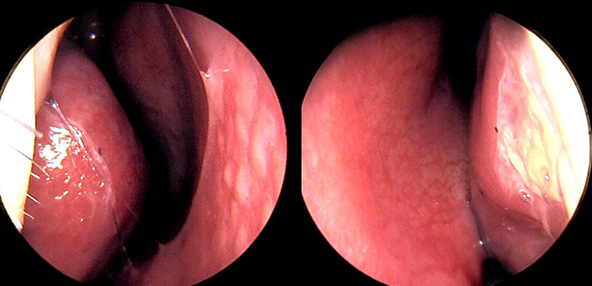

※ 비중격 비염 수술 후 생길 수 있는 부작용으로는 출혈, 감염, 염증이 있을 수 있습니다.

본 사진은 의료기관에서 진료를 본 환자이고, 전후 사진 인물이 동일인이며,동일조건에서 촬영이 되었습니다.